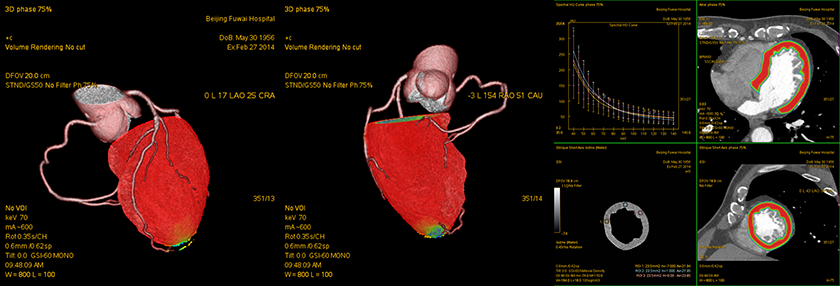

病例展示:Tree VR+透视图

左前降支(LAD)中段长条状硬化斑块(白色箭头)

病例展示:GSI Myocardium Perfusion

能谱心肌灌注显示:未见明显异常